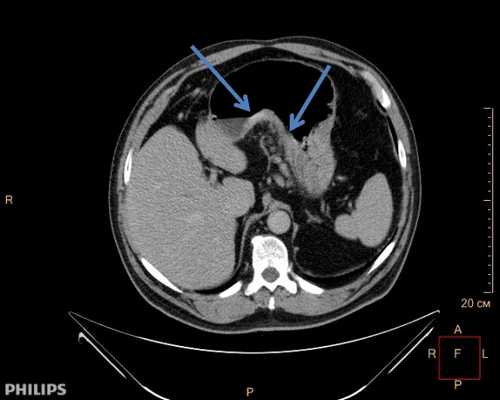

По данным ЭГДС, выполненной при поступлении: на фоне недостаточности кардии и неэрозивного рефлюкс-эзофагита на уровне 33 см от резцов по заднеправой стенке пищевода расположено экзофитное новообразование полиповидной формы размером 8×5 мм белесой окраски, выступающее в просвет на 4—5 мм, симптом шатра отрицательный (рис. 1, 2). Поверхность новообразования гладкая, сосудистый рисунок прослеживается.

Рис. 1. Новообразование по заднеправой стенке пищевода. Фото авторов.

Пациенту выполнена эндоскопическая ультрасонография (ЭУС): при сканировании мини-зондом UM-G 20-29 R частотой 20 MHz определяется гипоэхогенное образование овальной формы с четкими контурами, однородной консистенции, расположенное в толще слизистой оболочки и подслизистого слоя пищевода, при этом оно интимно прилежит к мышечной стенке, что не позволяет исключить инвазию образования в мышечный слой. Заключение ЭУС: неэпителиальное новообразование пищевода, исходящее из глубокого слоя слизистой оболочки и подслизистого слоя. При компьютерной томографии органов грудной клетки патологии не выявлено. По данным выполненной ранее щипцовой биопсии и гистологического исследования определена морфологическая принадлежность образования — шваннома.